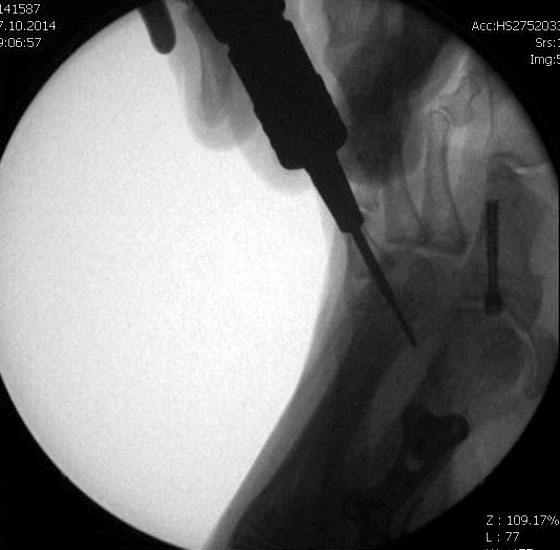

Jetzt erfolgt das Einbringen der Fräse im 45°-Winkel von distal dorsal nach proximal plantar. Auf steten Knochenkontakt mit der Kortikalis zur Vermeidung eines Weichteilinterponates sollte geachtet werden. In unserer Abteilung erfolgt vor Beginn der Osteotomie nun eine nochmalige Lagekontrolle der Fräse unter dem Bildwandler im dorsoplantaren Strahlengang. Eine zusätzliche laterale Aufnahme kann die Tiefe der eingebrachten Fräse in Bezug auf das zu osteomierende Metatarsale zeigen, ebenso ermöglicht sie eine Kontrolle des 45°-Winkels.